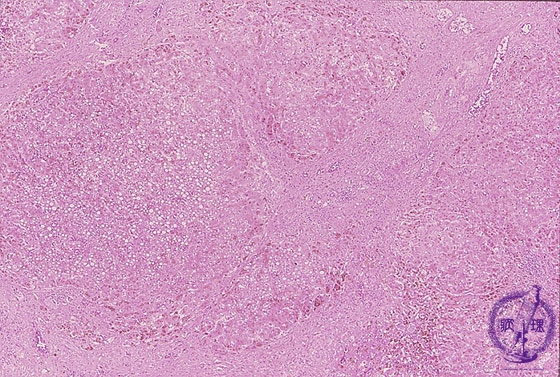

- 10.Liver

- (9)Liver hemochromatosis

Microscopic finding (HE stain, low power view): Regenerative nodule formation is accompanied by severe fibrosis with cirrhosis. Areas around regenerative nodules have a brownish tone due to hemosiderin deposition.